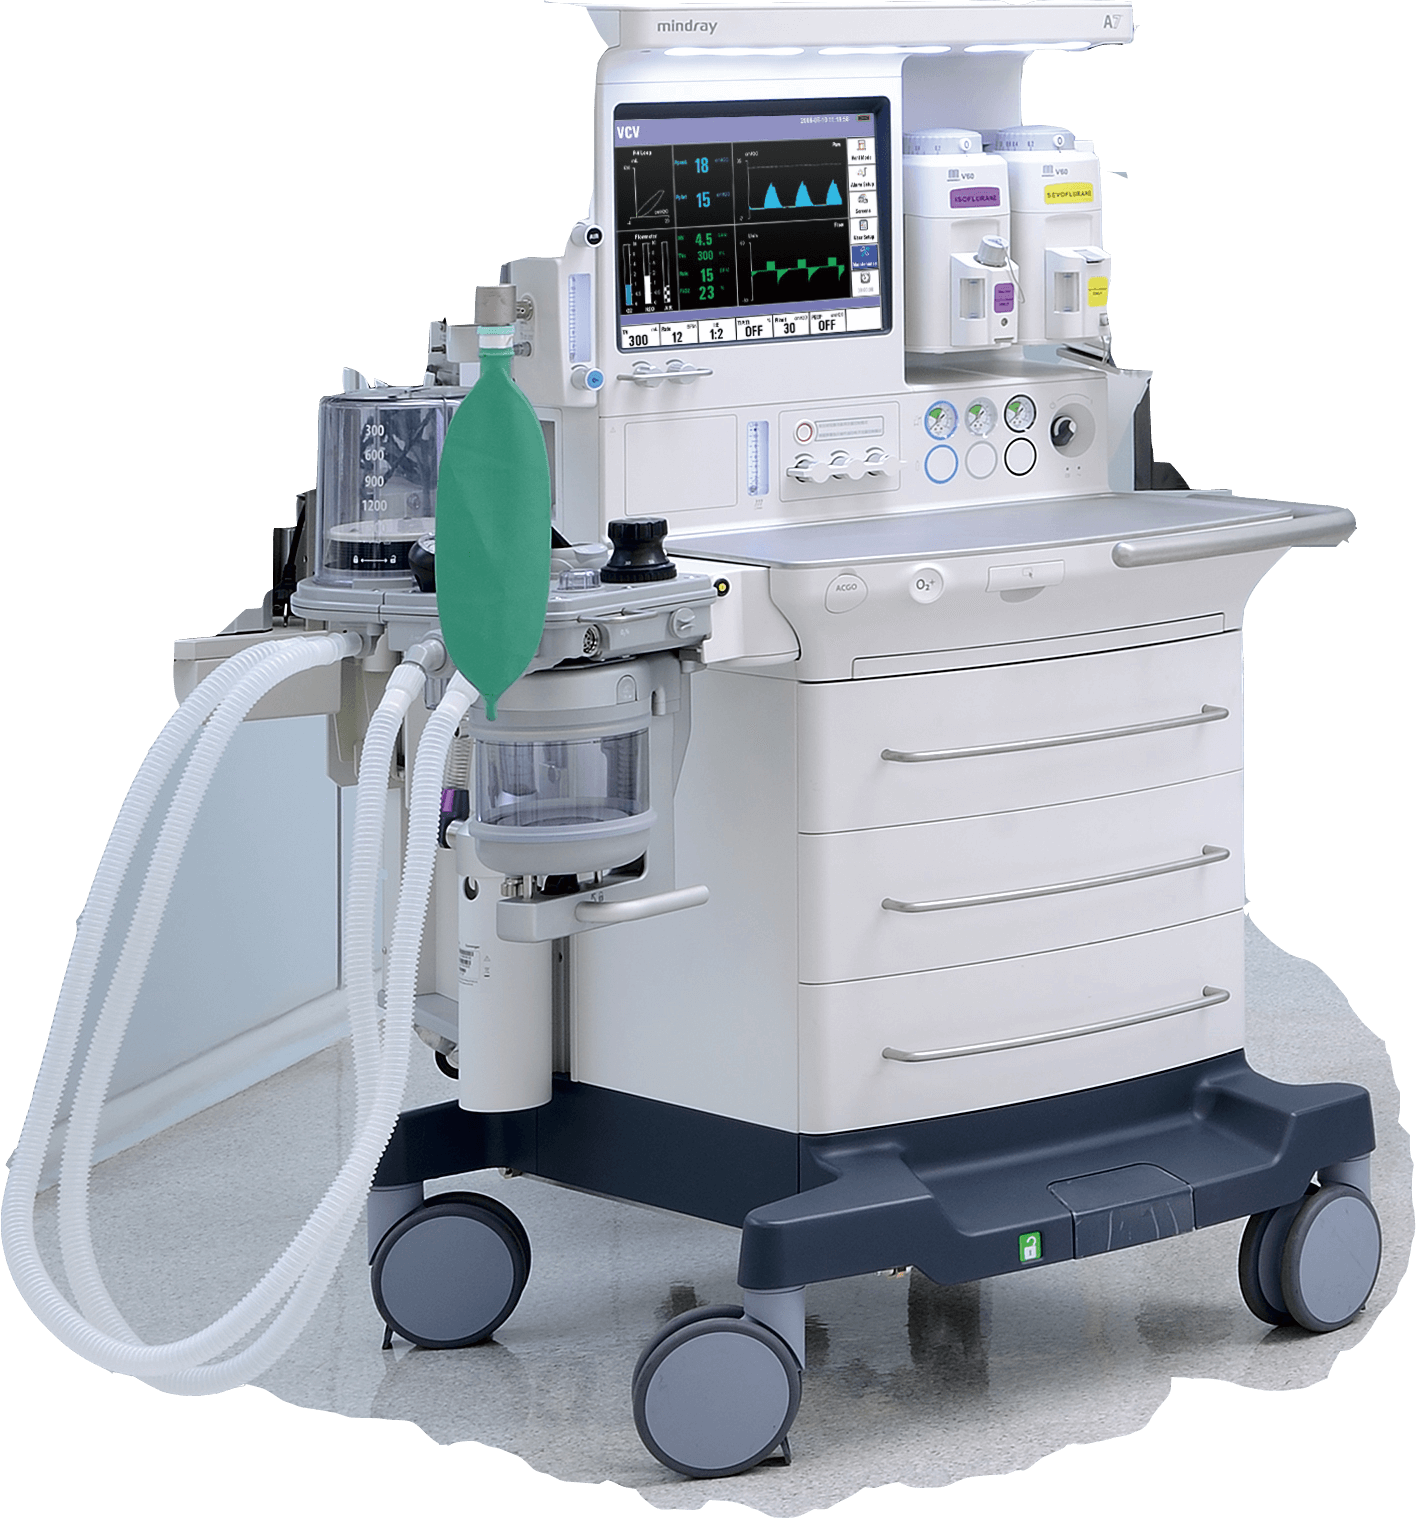

- ¬ЈAnaesthesia systems

Mindray Medical provides a full range of affordable perioperative product packages for a simple purchasing process, product range includes:

Helping to streamline clinical workflow, allowing healthcare providers to focus more on patient care.

For more than 25 years Mindray Medical has been partnering with healthcare providers to develop peri-operative solutions that fully meet the clinical requirements from induction to recovery, supporting clinicians during the most demanding situations while reducing their workloads.